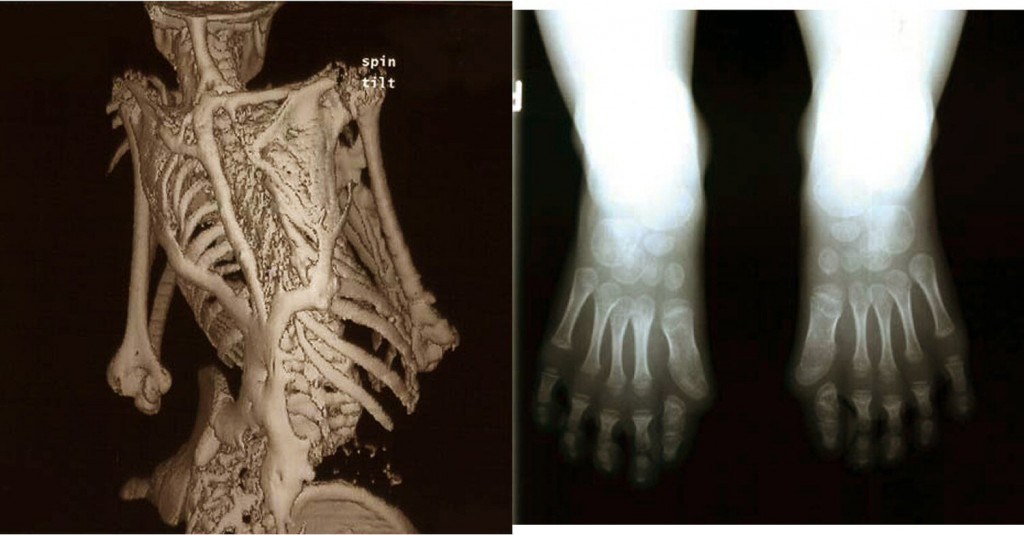

يشار إليه أحيانـا بمتلازمة الرجل الصخرة, وهو مرض شديد الندرة يصيب النسيج الضام، بحيث تحدث طفرة في طريقة إصلاح الضرر بالنسيج الضام بما فيه العضلات والأوتار والأربطة بحيث تتحول هذه الأنسجة إلى عظم في حال إصابتها أو تضررها، في الكثير من الحالات تتسبب الإصابات في المفاصل بتوقف المفصل تماما عن الحركة، وتفشل عمليات إزالة العظم الجديد الزائد في علاج الحالة حيث يقوم الجسم بمعالجة نفسه بتكوين عظم جديد في مكان الجرح، لا يوجد علاج لهذا المرض .